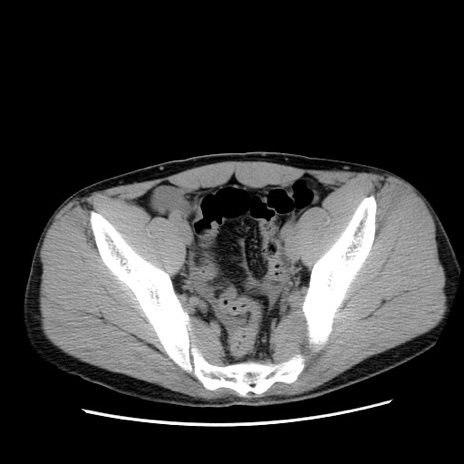

冠状断像

症例36(横断像)

【症例】20歳代 男性

【主訴】心窩部痛

【現病歴】今朝より上腹部痛あり。一旦軽快していたが再度出現したため救急要請。昨日夕に白身の魚を含む刺身を食べた。

【身体所見】BP 136/89mmHg、HR 74/min、BT 37.0℃、腹部:膨満、軟、心窩部に圧痛あり。反跳痛なし、筋性防御なし、腸雑音やや亢進あり。

【データ】WBC 17700、CRP 0.48